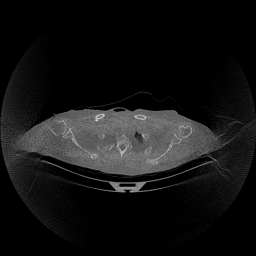

The results for simulated noisy data are shown in Fig. 2. The first and third rows display two representative slices from the test set, and the second and fourth rows present the corresponding error maps. The traditional WCE method suppresses cupping artifacts and recovers some missing anatomical structures but still shows noticeable deviations from the ground truth. Predictions from the four diffusion-based models demonstrate a markedly improved ability to restore anatomical structures. Among them, cDDPM fails to fully reconstruct the patient bed and retains residual noise in its outputs. This noise is attributable to an incomplete reverse denoising process rather than residual Poisson noise, as evidenced in our noise-free experiments (Fig. 5 in the Appendix). PatchDiffusion, diffusionGAN, and I2SB achieve similar visual quality, with I2SB producing the cleanest and most consistent reconstructions.

Quantitative results in Tab. V further confirm I2SB’s superiority over conventional deep learning methods such as FBPConvNet and Pix2pixGAN across RMSE, PSNR, and SSIM. Compared to other diffusion models—including cDDPM, PatchDiffusion, and cLDM—I2SB delivers higher image quality, while diffusionGAN achieves comparable quantitative performance. However, I2SB demonstrates a significant advantage in inference efficiency, as summarized in Tab. IV.

The experimental results on clinical head data are shown in Fig. 4. The reference images were reconstructed using the fast iterative shrinkage-thresholding algorithm (FISTA) with total variation regularization from non-truncated projection data. In the WCE reconstructions (Fig. 4(b)), severe truncation prevents accurate recovery of anatomical structures outside the FOV. Despite being trained solely on simulated data with a domain gap, all deep learning models can restore a substantial portion of the missing anatomy. Among them, the diffusion-based methods recover soft-tissue boundaries more faithfully than the conventional deep learning approach FBPConvNet, highlighting their stronger image generation capability. However, cDDPM reconstructions exhibit more noticeable noise than those from other methods, consistent with the simulated data results. The patchDiffusion model introduces artifacts within the FOV, likely due to its patch-wise processing strategy. While I2SB shares the same limitations as other diffusion models in perfectly restoring soft-tissue detail, it produces fewer residual noise patterns and fewer artifacts within the FOV boundaries. Overall, Fig. 4 demonstrates the strong efficacy of I2SB in reconstructing real CBCT data.